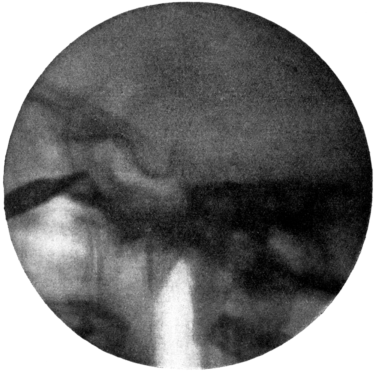

| 334. | Radiograph to show the Value of the Röntgen Rays | 639 |

| 335. | Radiograph showing Canula in the Frontal Sinus | 639 |